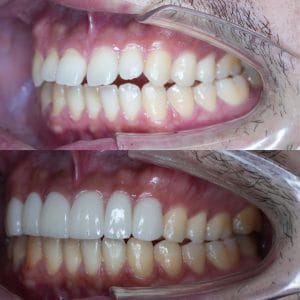

Case022

「歯の長さが短い、歯並びが歪んでる、表面が平面でカッコ悪い、歯茎が腫れている」ということを主訴に来院くださった患者様です。

セラミック矯正は歯科医の技術、センスで仕上がりが全く違うため、審美歯科の中でも担当する歯科医によって最も大きな差の出る診療です。

また、歯並びだけではなく顔貌(お顔立ち)まで綺麗にすることができる診療です。

歯茎の腫れは綺麗に歯を削り直して、正確に型を取り、

精密に作られたセラミックを適合よくセットしてあげることで、前医で入れてから1年以上腫れ続けてた歯茎が1週間で綺麗なピンク色に治りました。

形や並びに関しても、まず歯科医師が「どのような形にするか、どのように並べるか」をイメージしながら綺麗に削ることから始まります。

患者様の主訴通りに綺麗にできて喜んでいただきました。

当院では、患者様の主訴と、治療にかけられる費用、期間によって、ワイヤー矯正、インビザライン、インビザラインGo、セラミック矯正の中から治療法の特徴などをお話しし、その患者様に最適な治療を提案させて頂いております。